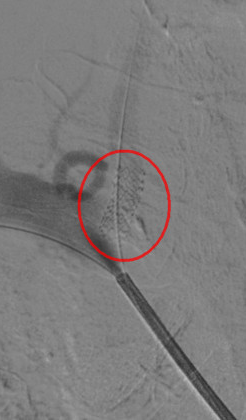

杨老伯的这次手术,也是我院首次使用药物涂层支架治疗椎动脉狭窄。术中,在贾军主任的指导下,董广宇副主任医师介入团队顺利实施椎动脉开口球囊成形及药物涂层支架置入手术,术后椎动脉开口基本恢复至正常大小。

手术非常成功。